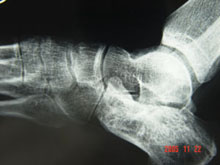

剥脱性骨软骨炎

(又名分离性骨软骨炎)

剥离性骨软骨炎是指骨软骨骨折或重复轻反复轻度外伤引起的血液运输障碍、骨软骨坏死脱...

骨关节及软组织CT、骨关节及肌肉MRI